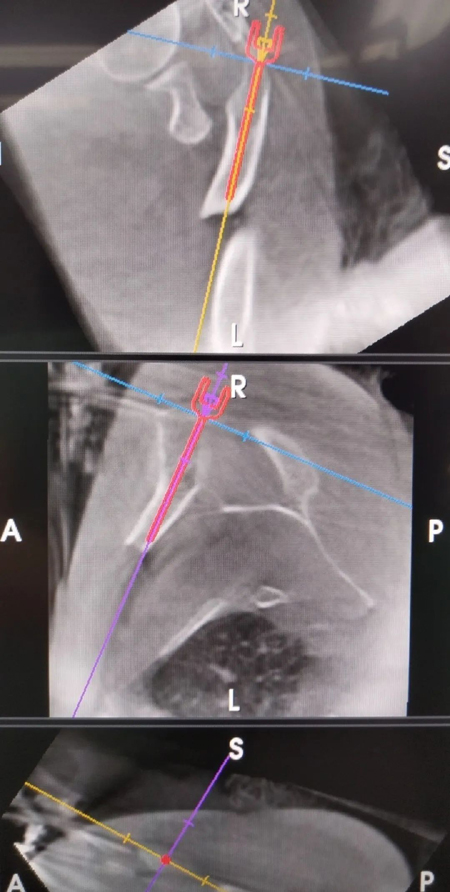

据了解,这名患者是在骑电动车时不慎摔倒,双手着地,致双肩部疼痛伴活动受限。患者伤后来我院急诊就诊,结合病史、查体及X线片检查,确诊为双侧锁骨骨折。急诊进行锁骨带固定后,患者住院手术治疗。手术中,专家团队在肩峰固定示踪器,术中三维CT规划弹性髓内钉入钉点及方向。在机器臂引导下精准选择最合适的入钉点,复位满意后,置入3.0弹性髓内钉。术后患者恢复良好。

▲蒋协远院长指导手术路径规划